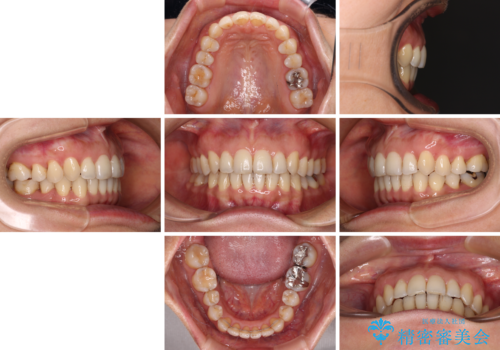

矯正治療の後戻り インビザライン・ライトによる矯正治療

- 11ヶ月

- 矯正治療の後戻りを気にして来院された患者様です。

後戻りは軽微であったので、インビザライン・ライトにより矯正治療を行うこととしました。

インビザライン・ライトは提供されるマウスピースの数に制限があり、通常のタイプよりもマウスピース提供期間が短くなっている一方、安価に治療を行うことができるプランです。

治療のゴールも変更できないため、軽微な歯列不正や、後戻り改善などに適しています。